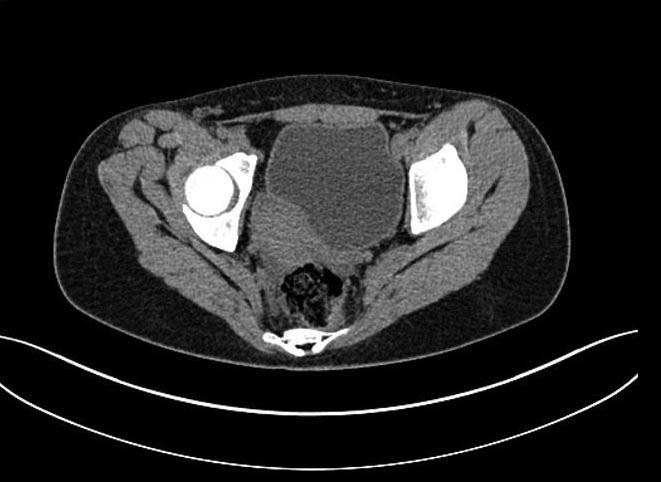

Здравствуйте.Помогите с диагнозом и тактикой лечения.

Больная 15 лет. Жалобы: на укорочение правой нижней конечности, хромоту. Анамнез: Со слов

болеет с детства, травму отрицает. Ранее за медицинской помощью не обращалась. Последние 2

года отмечает резкое укорочение конечности. Локально: При осмотре отмечается умеренное

искривление позвоночника во фронтальной плоскости, умеренная асимметрия лопаток и

надплечий. Скошенность таза. Отмечается укорочение правой нижней конечности на 3 см.

Движения в тазобедренном и коленном суставах в полном объеме. Нейрососудистых нарушений в

периферических отделах нет.